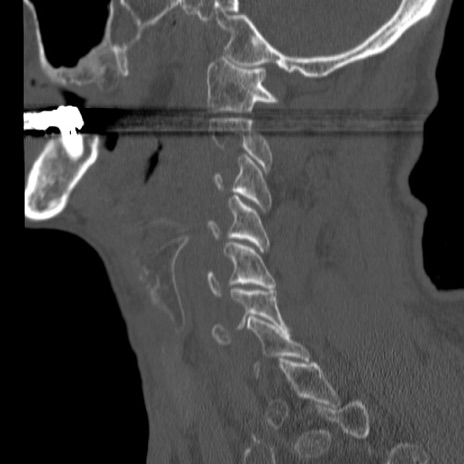

症例46 頚椎CT(矢状断像)

【症例】80歳代男性

【主訴】両側頚部〜上肢のしびれ

【現病歴】昨日、自宅内で転倒、その後より上記症状あり。意識障害なし。

【身体所見】両側上肢のallodynia(熱痛覚過敏)あり。MMTおよびDTRは正確な所見取れず。両上肢の挙上はなんとか可能。

異常所見と診断は?